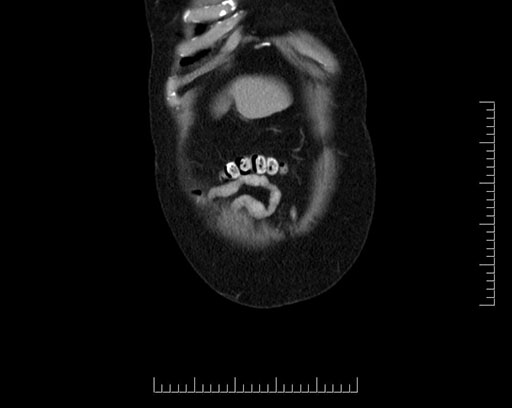

Axial - stented